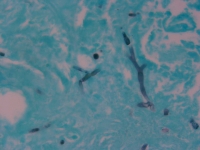

| Substrate: | ulcer on left calf, male 90 yr; biopsy + for hyphae with few septa and thick-walled yeast forms | Location: | USA Nebraska, Omaha, University of Nebraska Medical Center (GEO: 41.255,-95.976) |

| Characters: | CULTURE CONDITIONS no zygospores in matings with UAMH 8306 or 8307 - // HUMAN/ ANIMAL PATHOGEN primary cutaneous infection - Iwen PC, Sigler L, Freifeld AG, J Clin Microbiol 45:636-640, 2007 // MOLECULAR SYSTEMATICS ITS sequence comparison showed 99% similarity with GenBank sequence for Mucor circinelloides - (Click for publications citing UAMH 10385) |